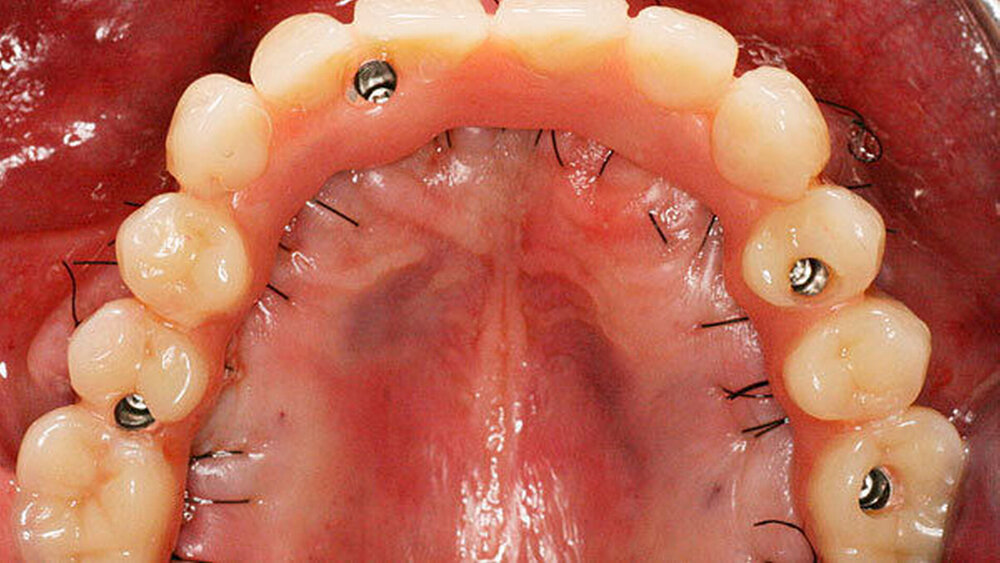

Bei der Sofortversorgung nach dem All-on-4 Konzept (Abbildung 1a-d) werden die frontalen Implantate gerade inseriert und axial belastet, die distalen in der Regel anguliert (Abbildung 2). Durch die Angulation kann ein externer Sinuslift im Oberkiefer umgangen und eine ausreichende Primärstabilisation für eine Sofortversorgung erreicht werden. Im Unterkiefer verhindert das Foramen mentale bei gerader Insertion häufig eine dorsale Positionierung der Implantate. Durch die Angulation der distalen Implantate werden das Belastungspolygon optimiert und ausgeprägte distale Cantilever (Extensionsbrücken) vermieden.

Entscheidend für den Erfolg dieses Konzepts ist die Hygienefähigkeit des Zahnersatzes. Die Basis des Zahnersatzes sollte konvex gestaltet werden und nur linear zum Kieferkamm Kontakt haben (Abbildung 1d). Diese Gestaltung erleichtert eine einfache Mundhygiene mit Interdentalbürsten und Zahnseide. Die Hygienefähigkeit einer All-on-4 Konstruktion ist somit vergleichbar mit einer Stegversorgung. Entscheidend für die Ästhetik ist die präoperative Feststellung der Lippenlachlinie. Diese entscheidet über die Resektionshöhe des Kieferkamms. Die Ästhetik wird bei dieser Versorgungsart ausschließlich über den Zahnersatz erreicht (Abbildung 1d). Die „rote Ästhetik“ kann durch die Verwendung von Prothesenkunststoff individuell und natürlich gestaltet werden. Der Zahnersatz ist bei diesem Konzept okklusal mit den Implantaten verschraubt (Abbildung 1c). Bei Notwendigkeit, zum Beispiel bei Reparaturen, kann dieser durch den Behandelnden leicht ab- genommen werden.